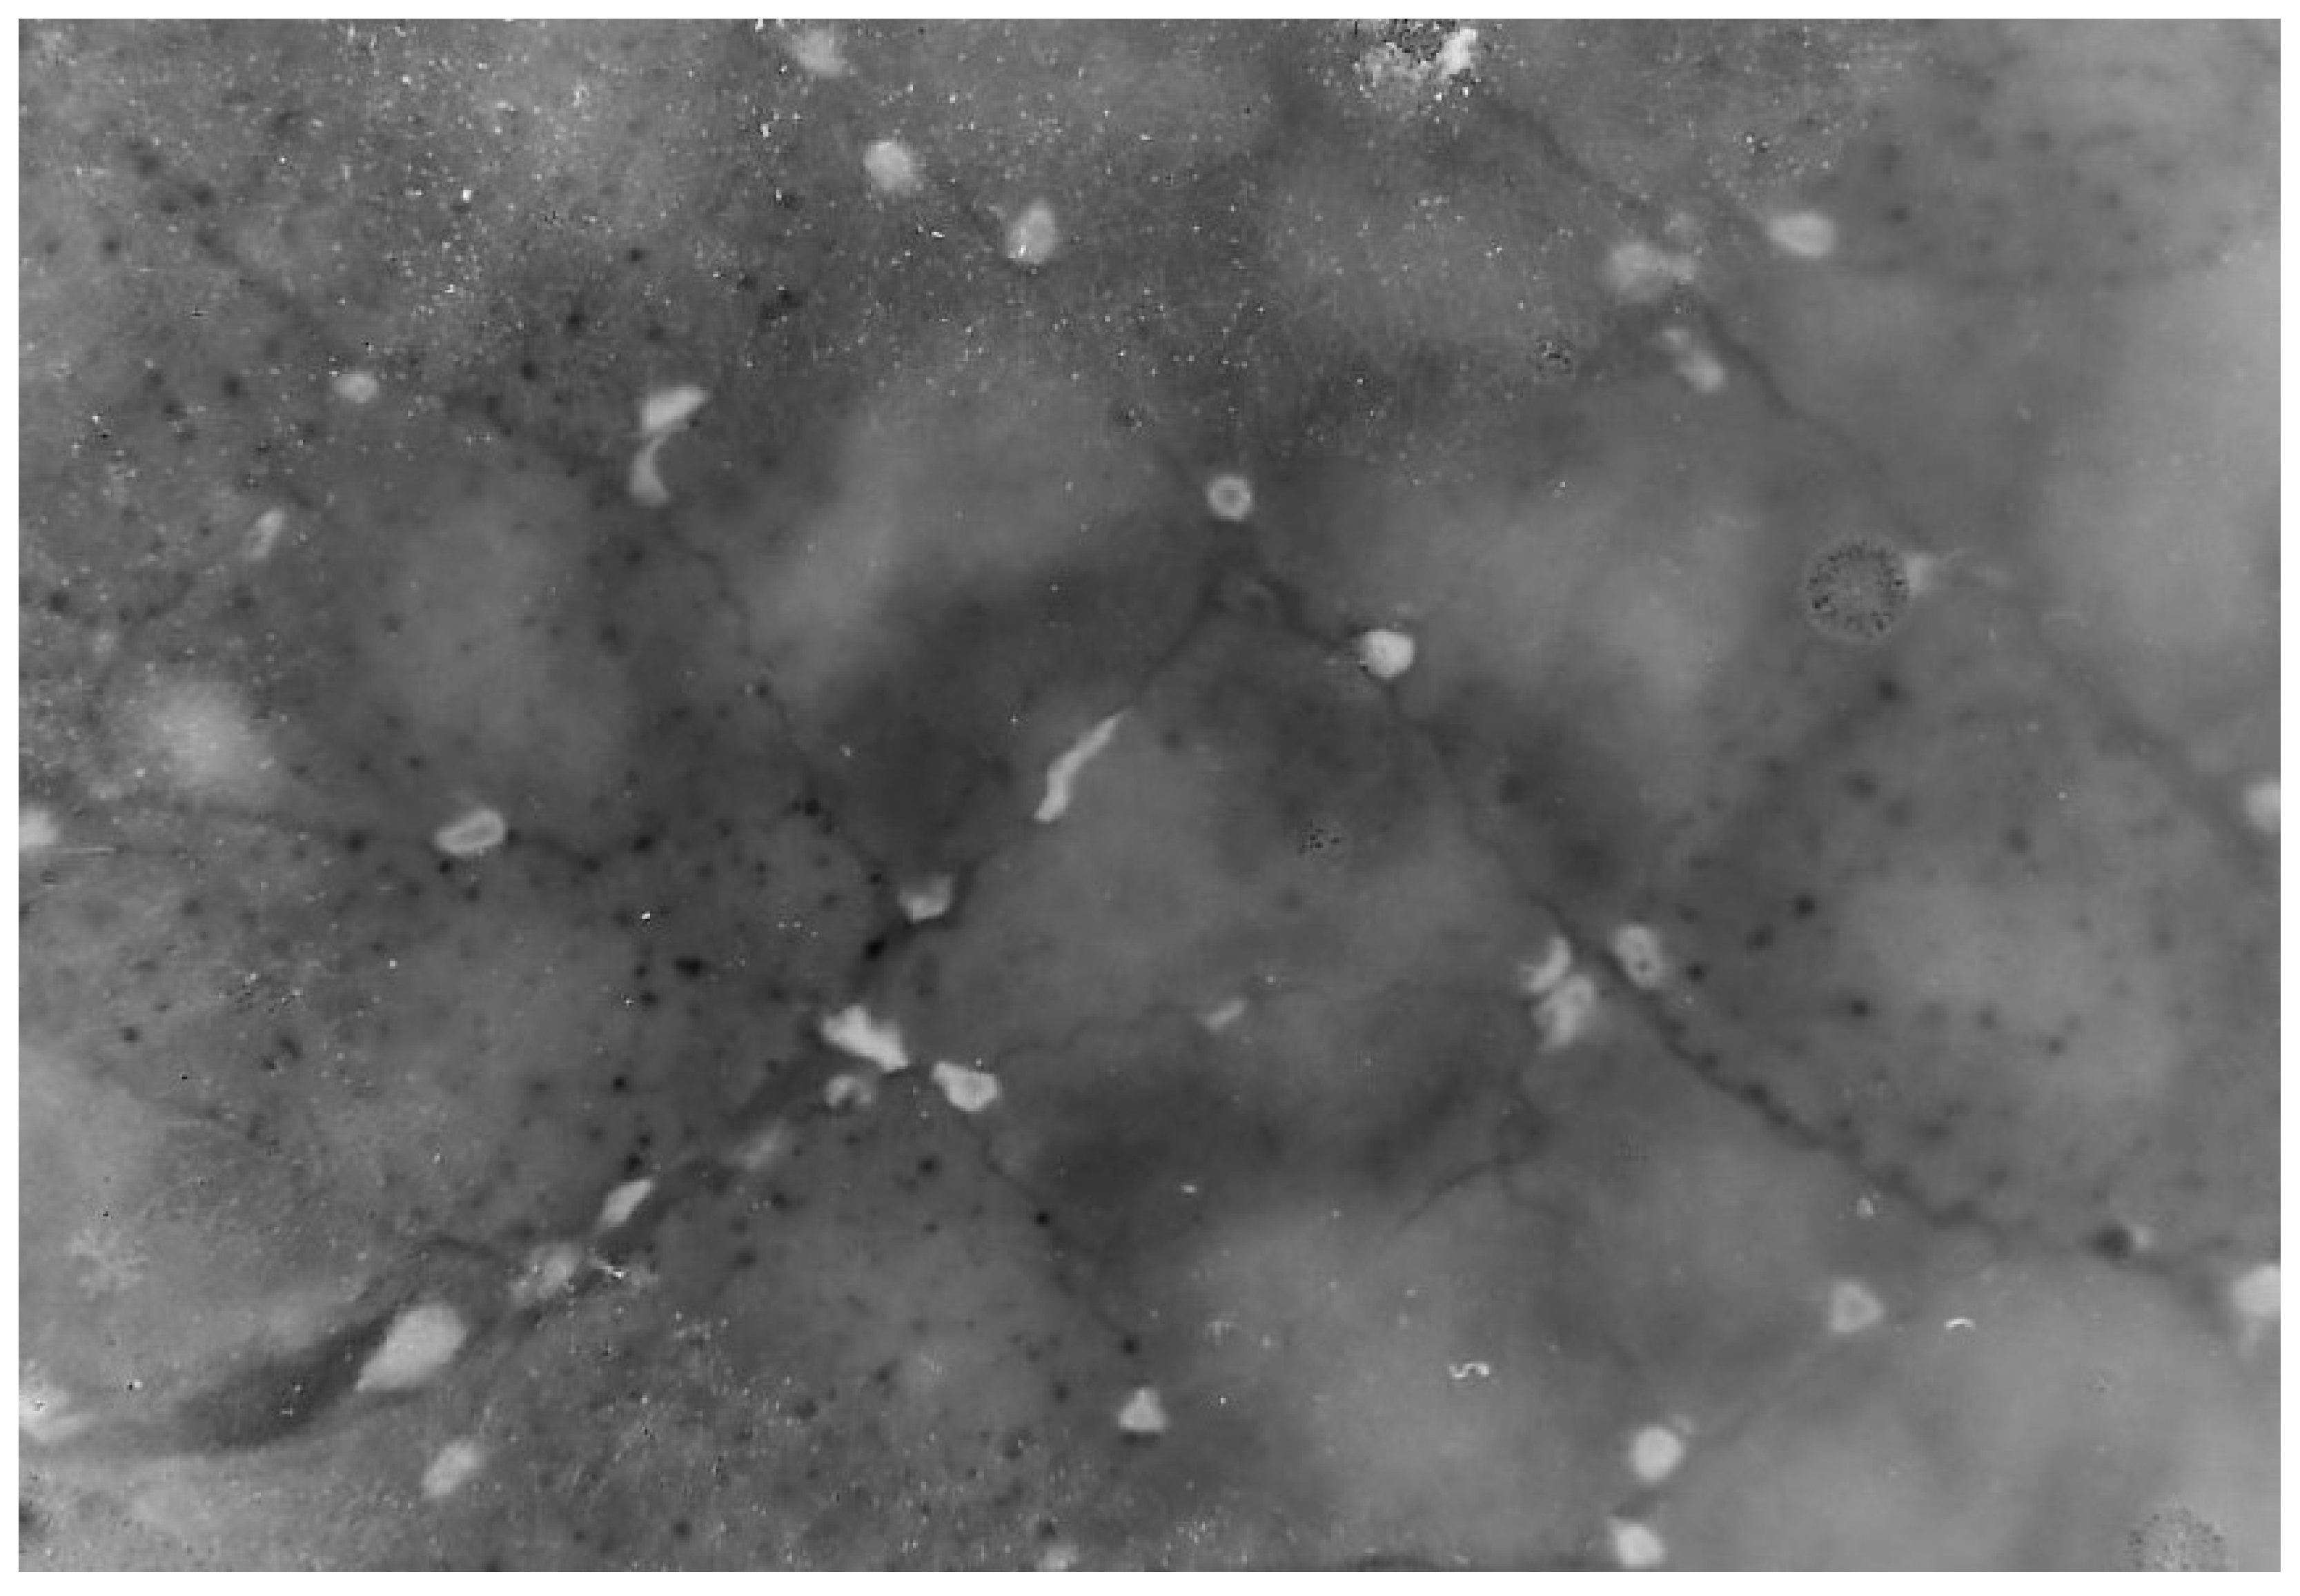

18. Mitochondrial Myopathy

19. Megaconial Mitochondrial Myopathy

20. Multiple acyl-CoA Dehydrogenation and CoQ10 Deficiency

30. Myoclonus Epilepsy with Ragged Red Fibers (MERRF)